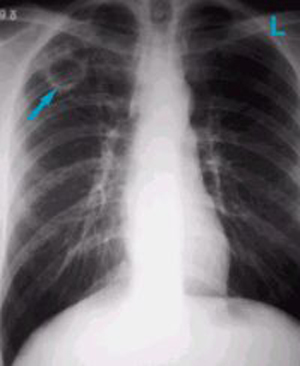

тонкостенная полость распада

Рис. 11. На рентгенограмі у верхній частці правої легені тонкостінна порожнину розпаду.